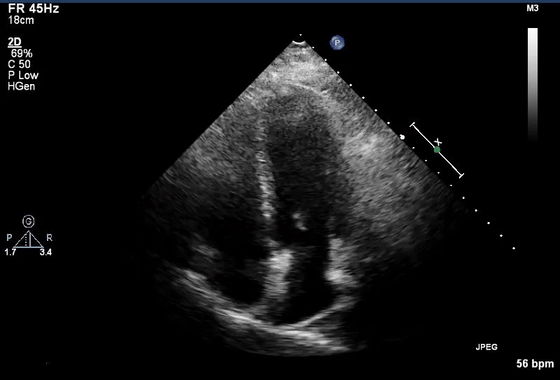

7、近场杂波

由于探头换能器本身的高振幅振荡,近场结构有时会被遮蔽,造成所谓的近场杂波。这在怀疑有心尖室血栓的病例中尤其重要(图7,视频10)。谐波成像的引入和换能器设计技术的进步已经减少了这种伪影的发生。

图7 心尖四腔视图中的近场杂波(箭头),疑似心尖血栓。(视频10)显示正常的心尖心肌动力学,杂乱回波和心肌运动之间没有关系。